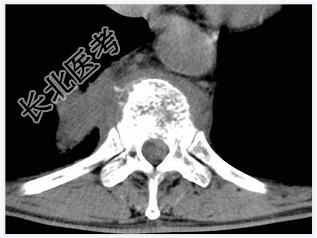

- [材料题] 男,32岁,低热、腰背痛,活动受限。

- 简答题1、结合CT检查,最可能的诊断是?

- 简答题2、椎体结核的典型症状是什么?